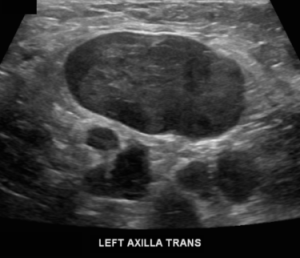

The mammogram is reviewed, and besides the abnormal lymph nodes, no other suspicious finding is seen in the breasts. An ultrasound is performed of the axilla:

Explanation: There are multiple abnormal lymph nodes in the left axilla, and so far no evidence of any abnormality in the left breast. The presence of unilateral axillary lymphadenopathy must be presumed to be metastatic breast cancer until proven otherwise. These findings must be deemed suspicious and biopsy of one of the lymph nodes should be performed. Whenever possible, the BI-RADS assessment and recommendation should be concordant.